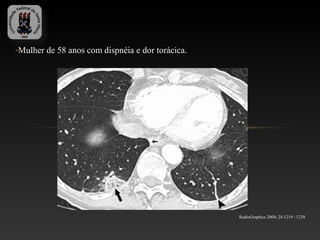

-Mulher de 58 anos com dispnéia e dor torácica.

RadioGraphics 2004; 24:1219 –1238